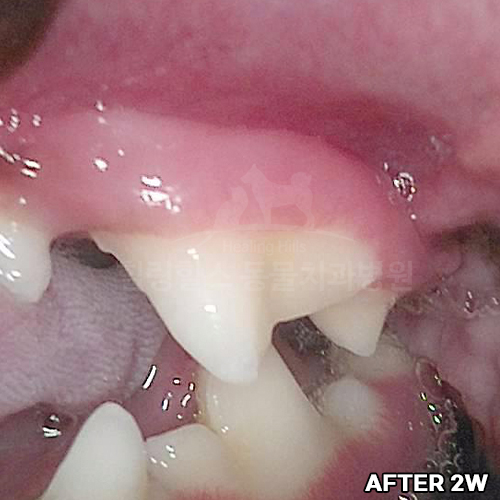

최고 난이도 강아지신경치료 - 꽉막힌 근관&치수괴사! 커다란 반려견치근단농양! 녹아내린 턱뼈! 치통으로 사나워진 모습! 강아지 신경치료 & 치주치료 한달 뒤 좋아졌어요!